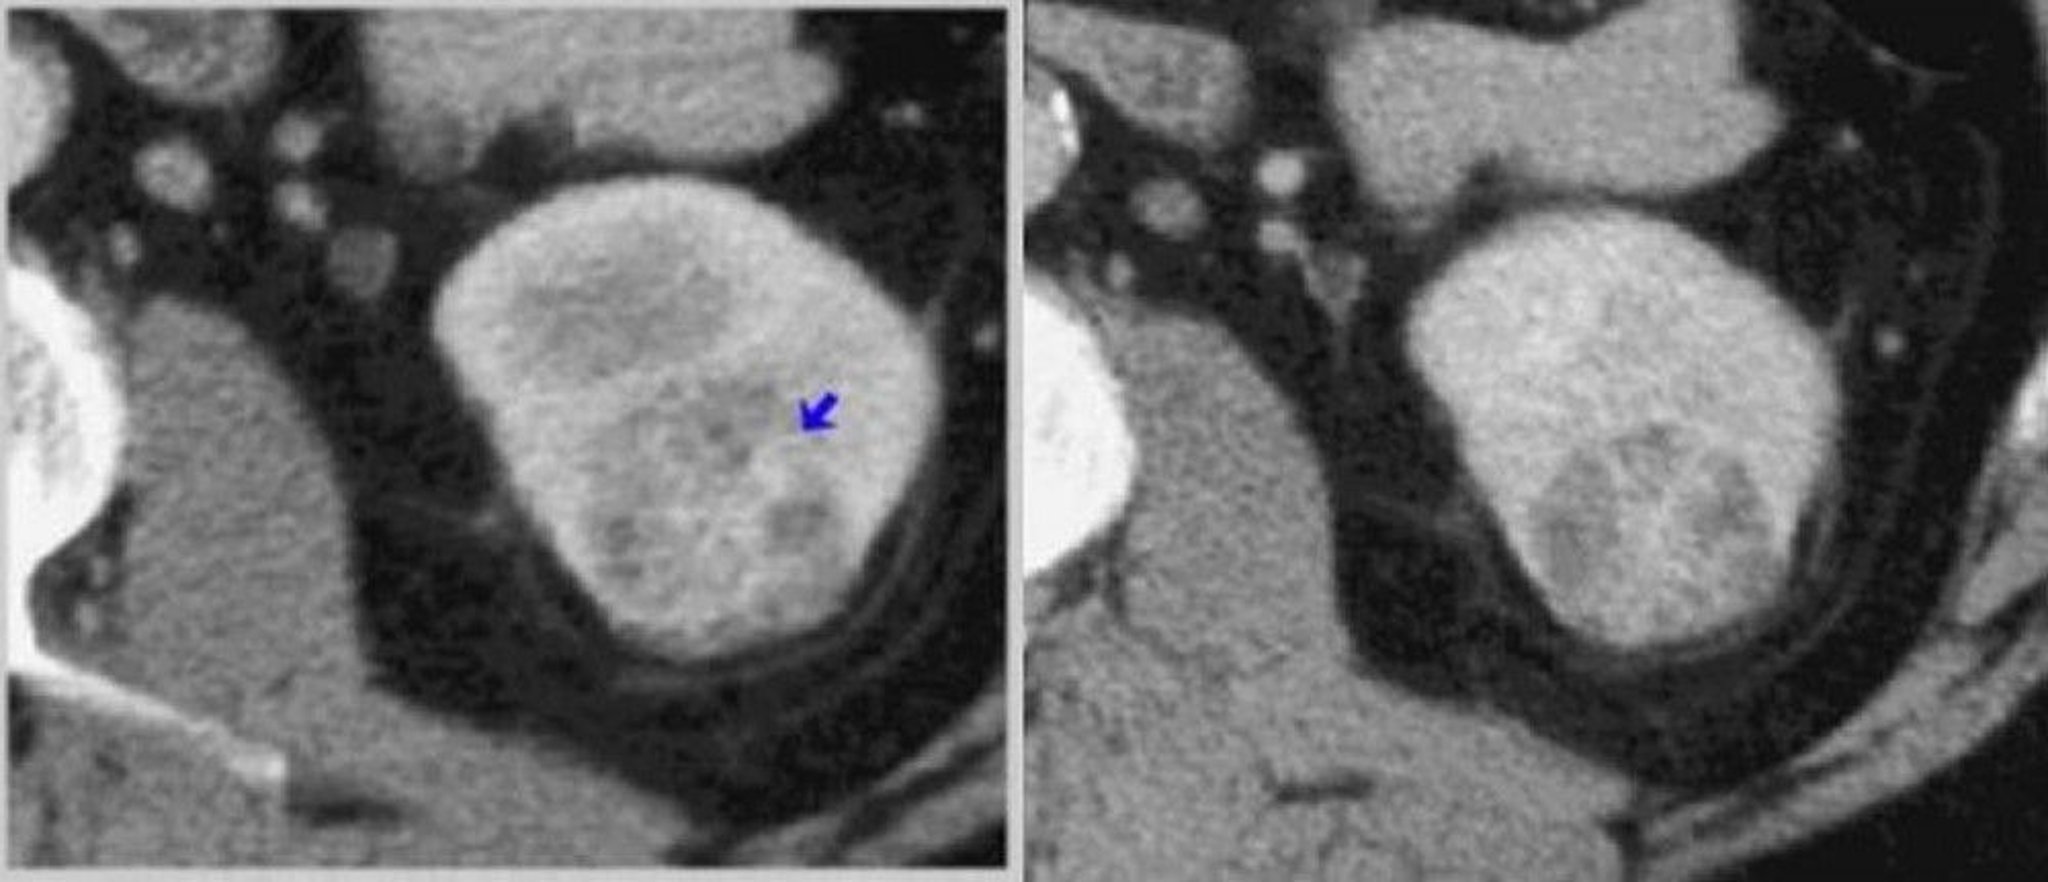

Tomografía computarizada con contraste del riñón (fases corticomedular y nefrogénica)

A la izquierda, una TC en fase corticomedular muestra un tumor con realce de contraste heterogéneo (flecha). A la derecha, una TC en fase nefrográfica define mejor el tumor.